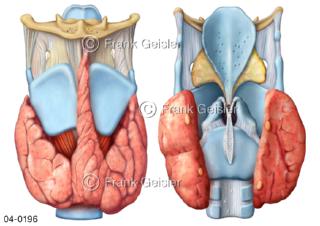

Bildergalerie Topografie Organe

Bilder zur topografischen Anatomie, die Lage der Organe und die Strukturen nach ihren räumlichen Lagebeziehungen zueinander, Übersicht der inneren Organe im Kopf und im Rumpf, Topografie der Organe im Brustraum (Thorax) und im Bauchraum (Abdomen)